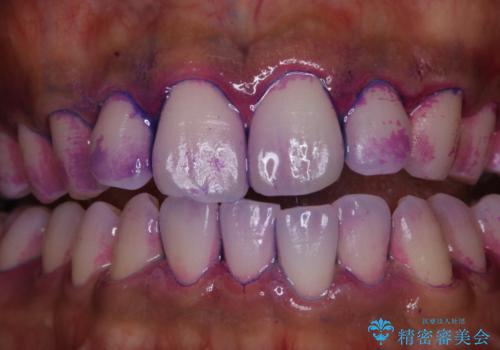

- 特に症状など気になるところはないが、メンテナンスして欲しいとのことでした。染め出しをしてのブラッシング指導とPMTC30分コースを行いました。

染め出しをすると、現在付着しているプラークを確認できて、今後の正しいハミガキの方法を知るチャンスとなります。